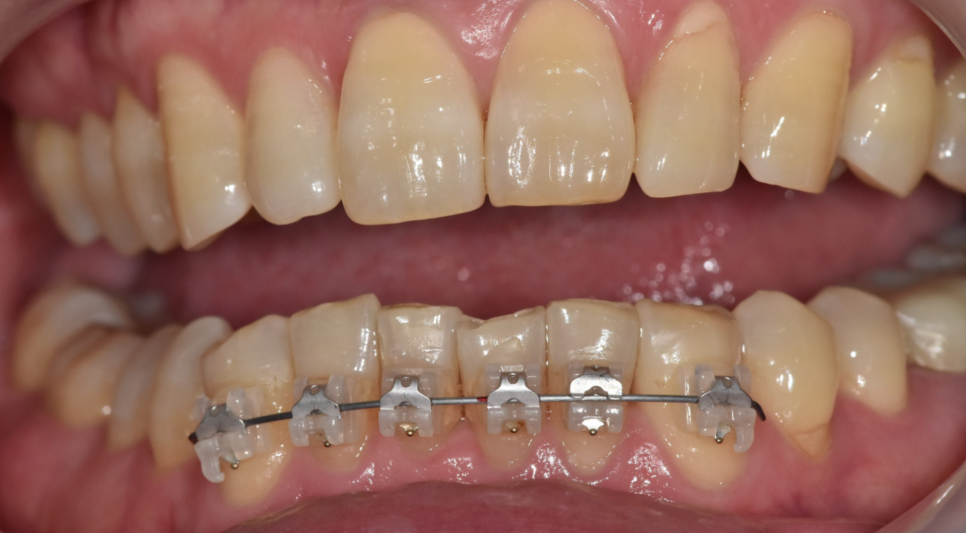

250425 부분 교정도 고려해볼 수 있습니다 .